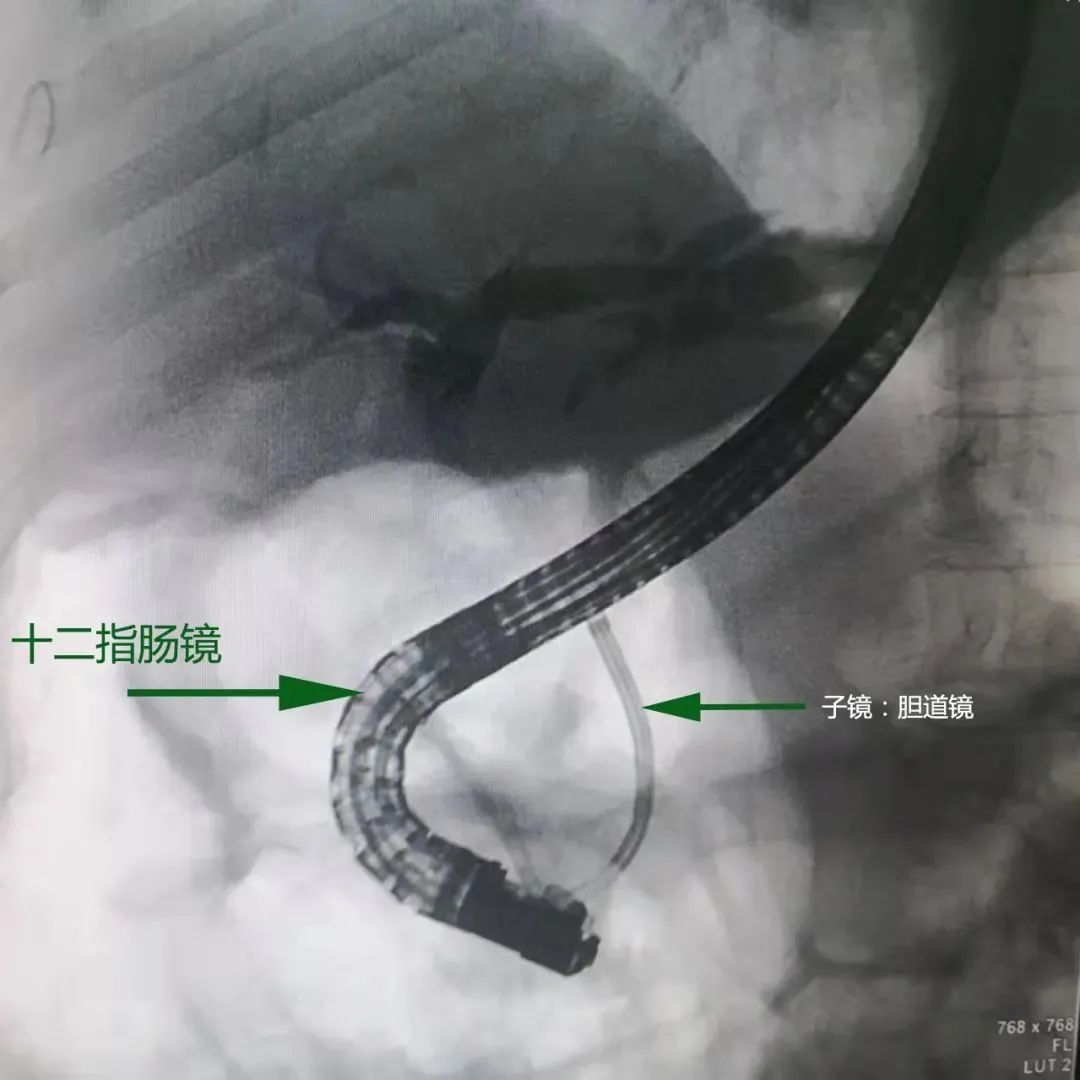

“双镜”示意图

最值得一提的是,该技术在治疗难治性胆总管结石上,有着“奇效”。前期检查发现,患者姚阿婆的胆总管结石具有胆管内结石多发、结石密度较高,且填满胆管下端,传统手术施展空间太小。“传统手术只能通过造影和切开胆总管来找到并治疗病灶,现在十二指肠镜的基础上,加用子镜——胆道镜,就可以直视碎石,并用激光进行粉碎,腾出取石网篮展开空间,一次取尽多发结石。”何承祥补充道,整个手术用时不到2小时。